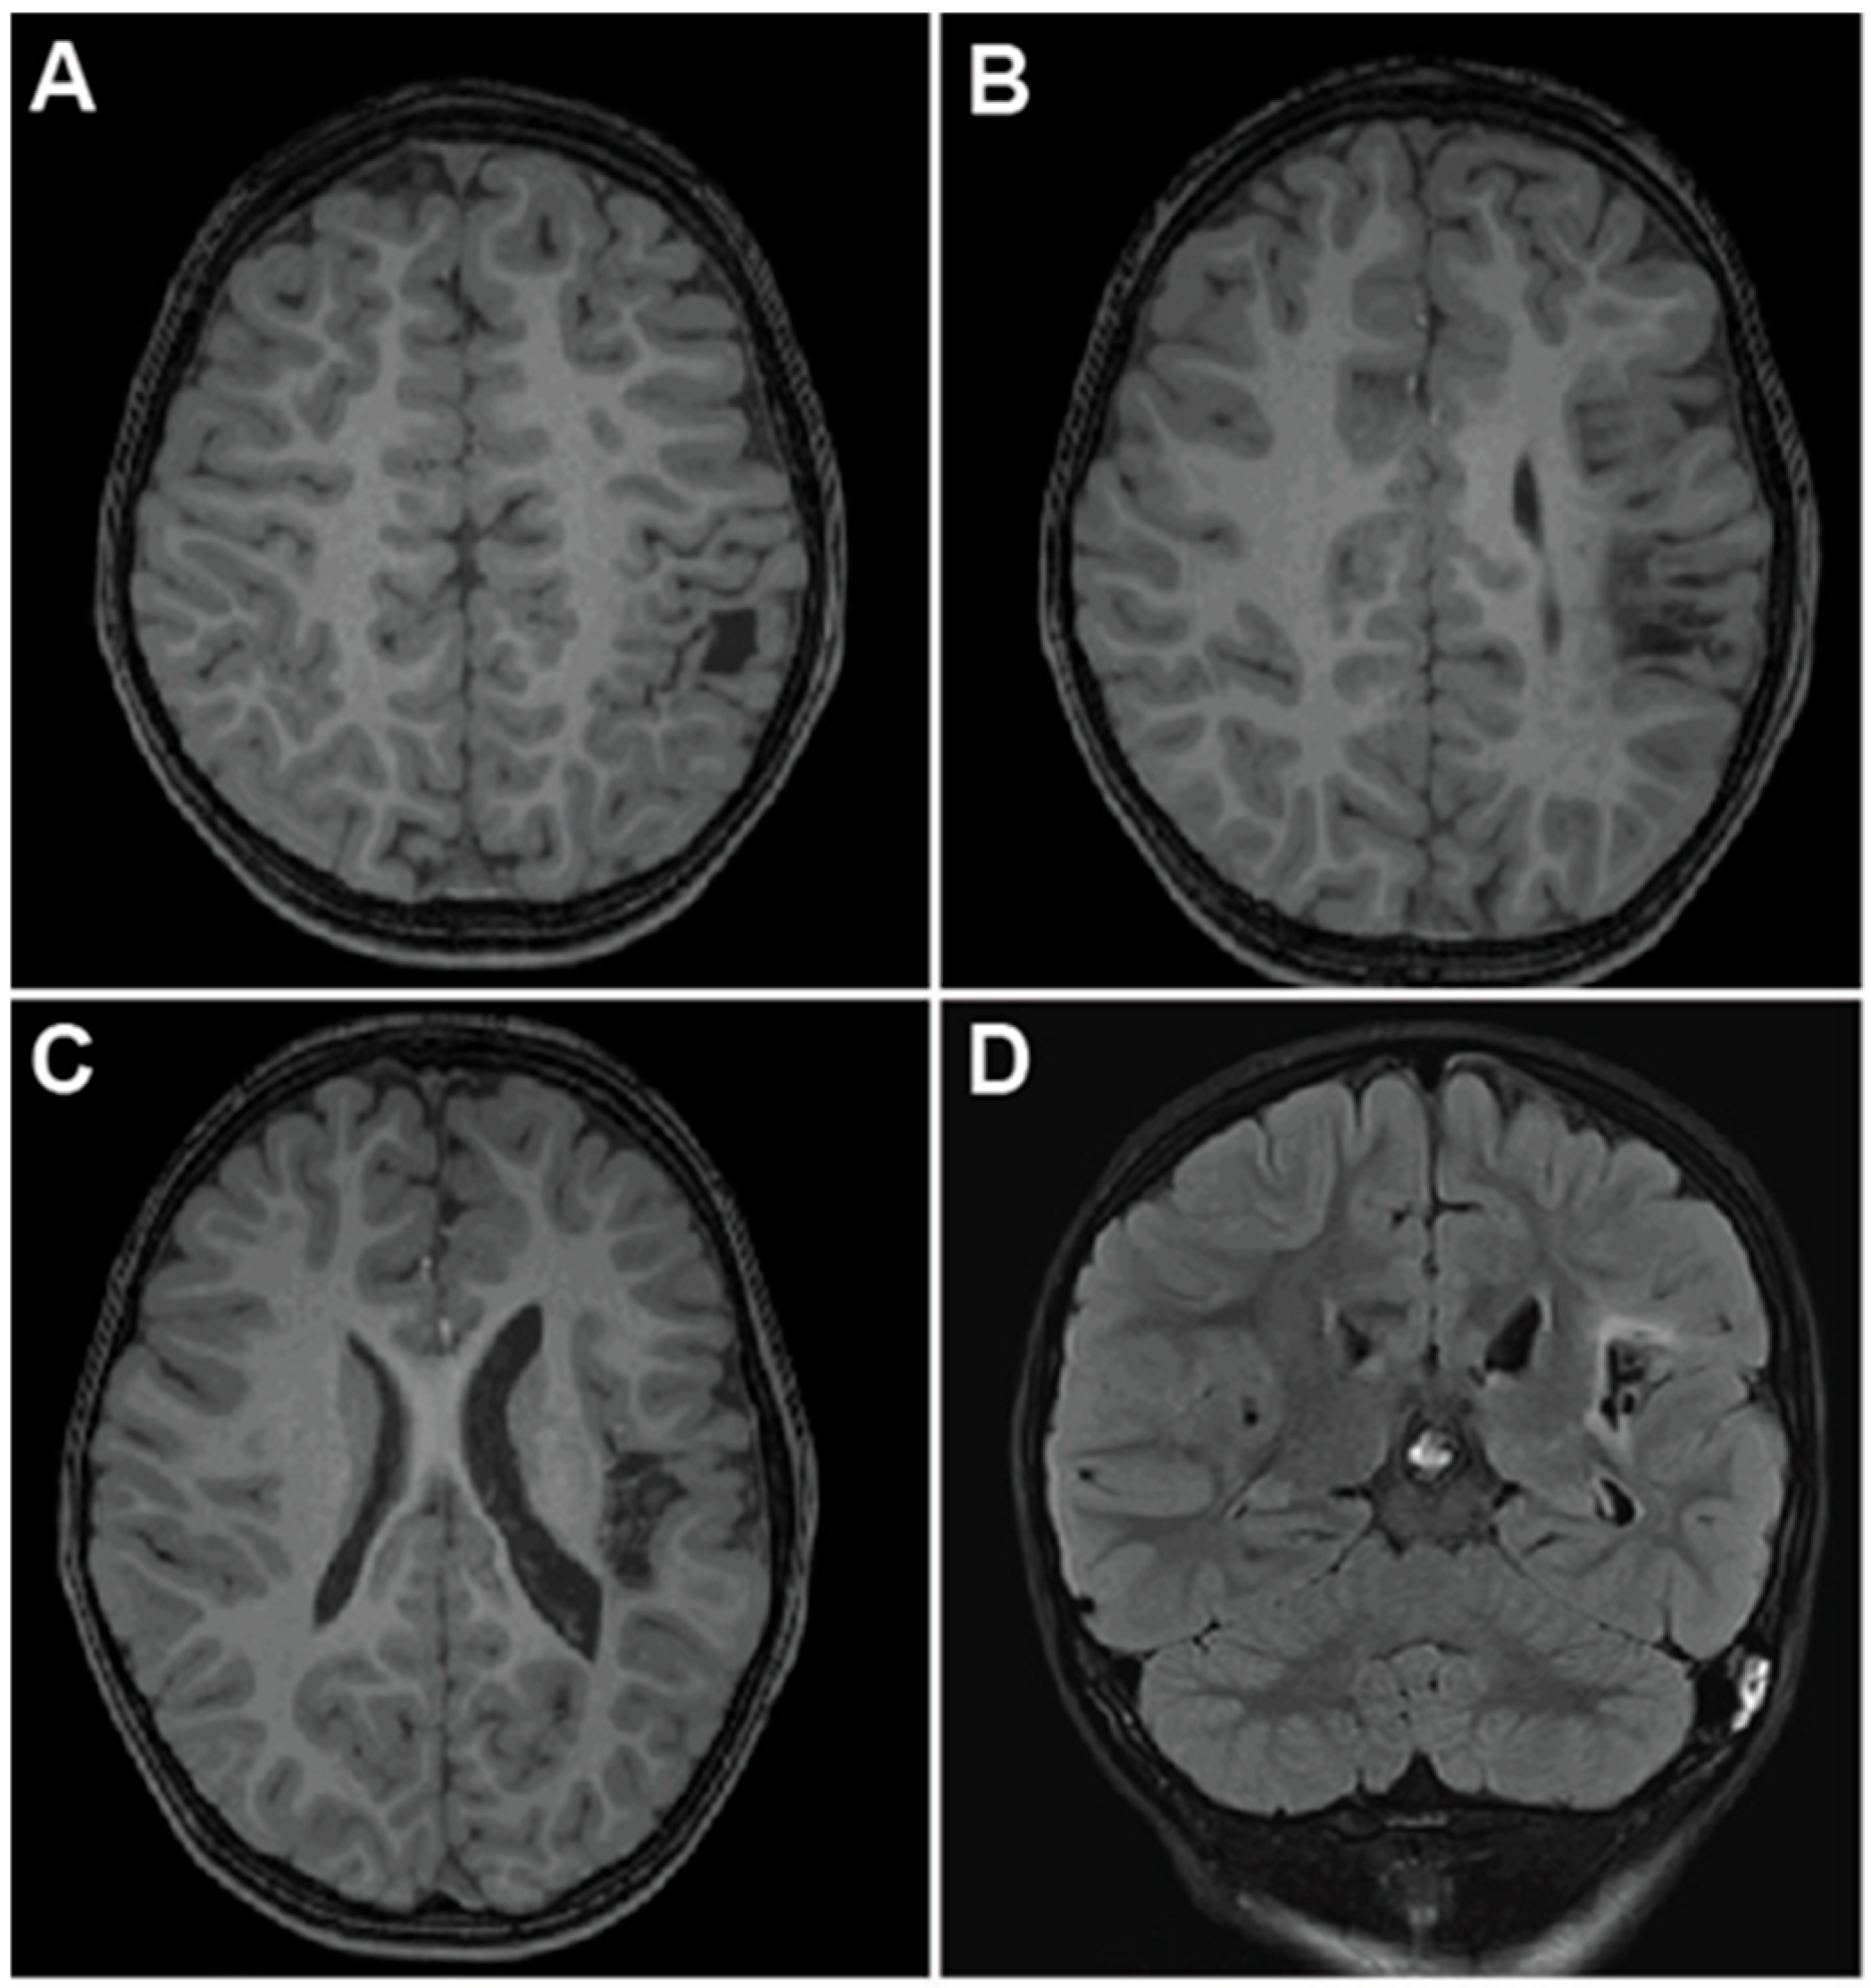

2.3. Case 3—Trans-Opercular Approach for Infarct Spanning Left Posterior Insula and Parietal Lobe